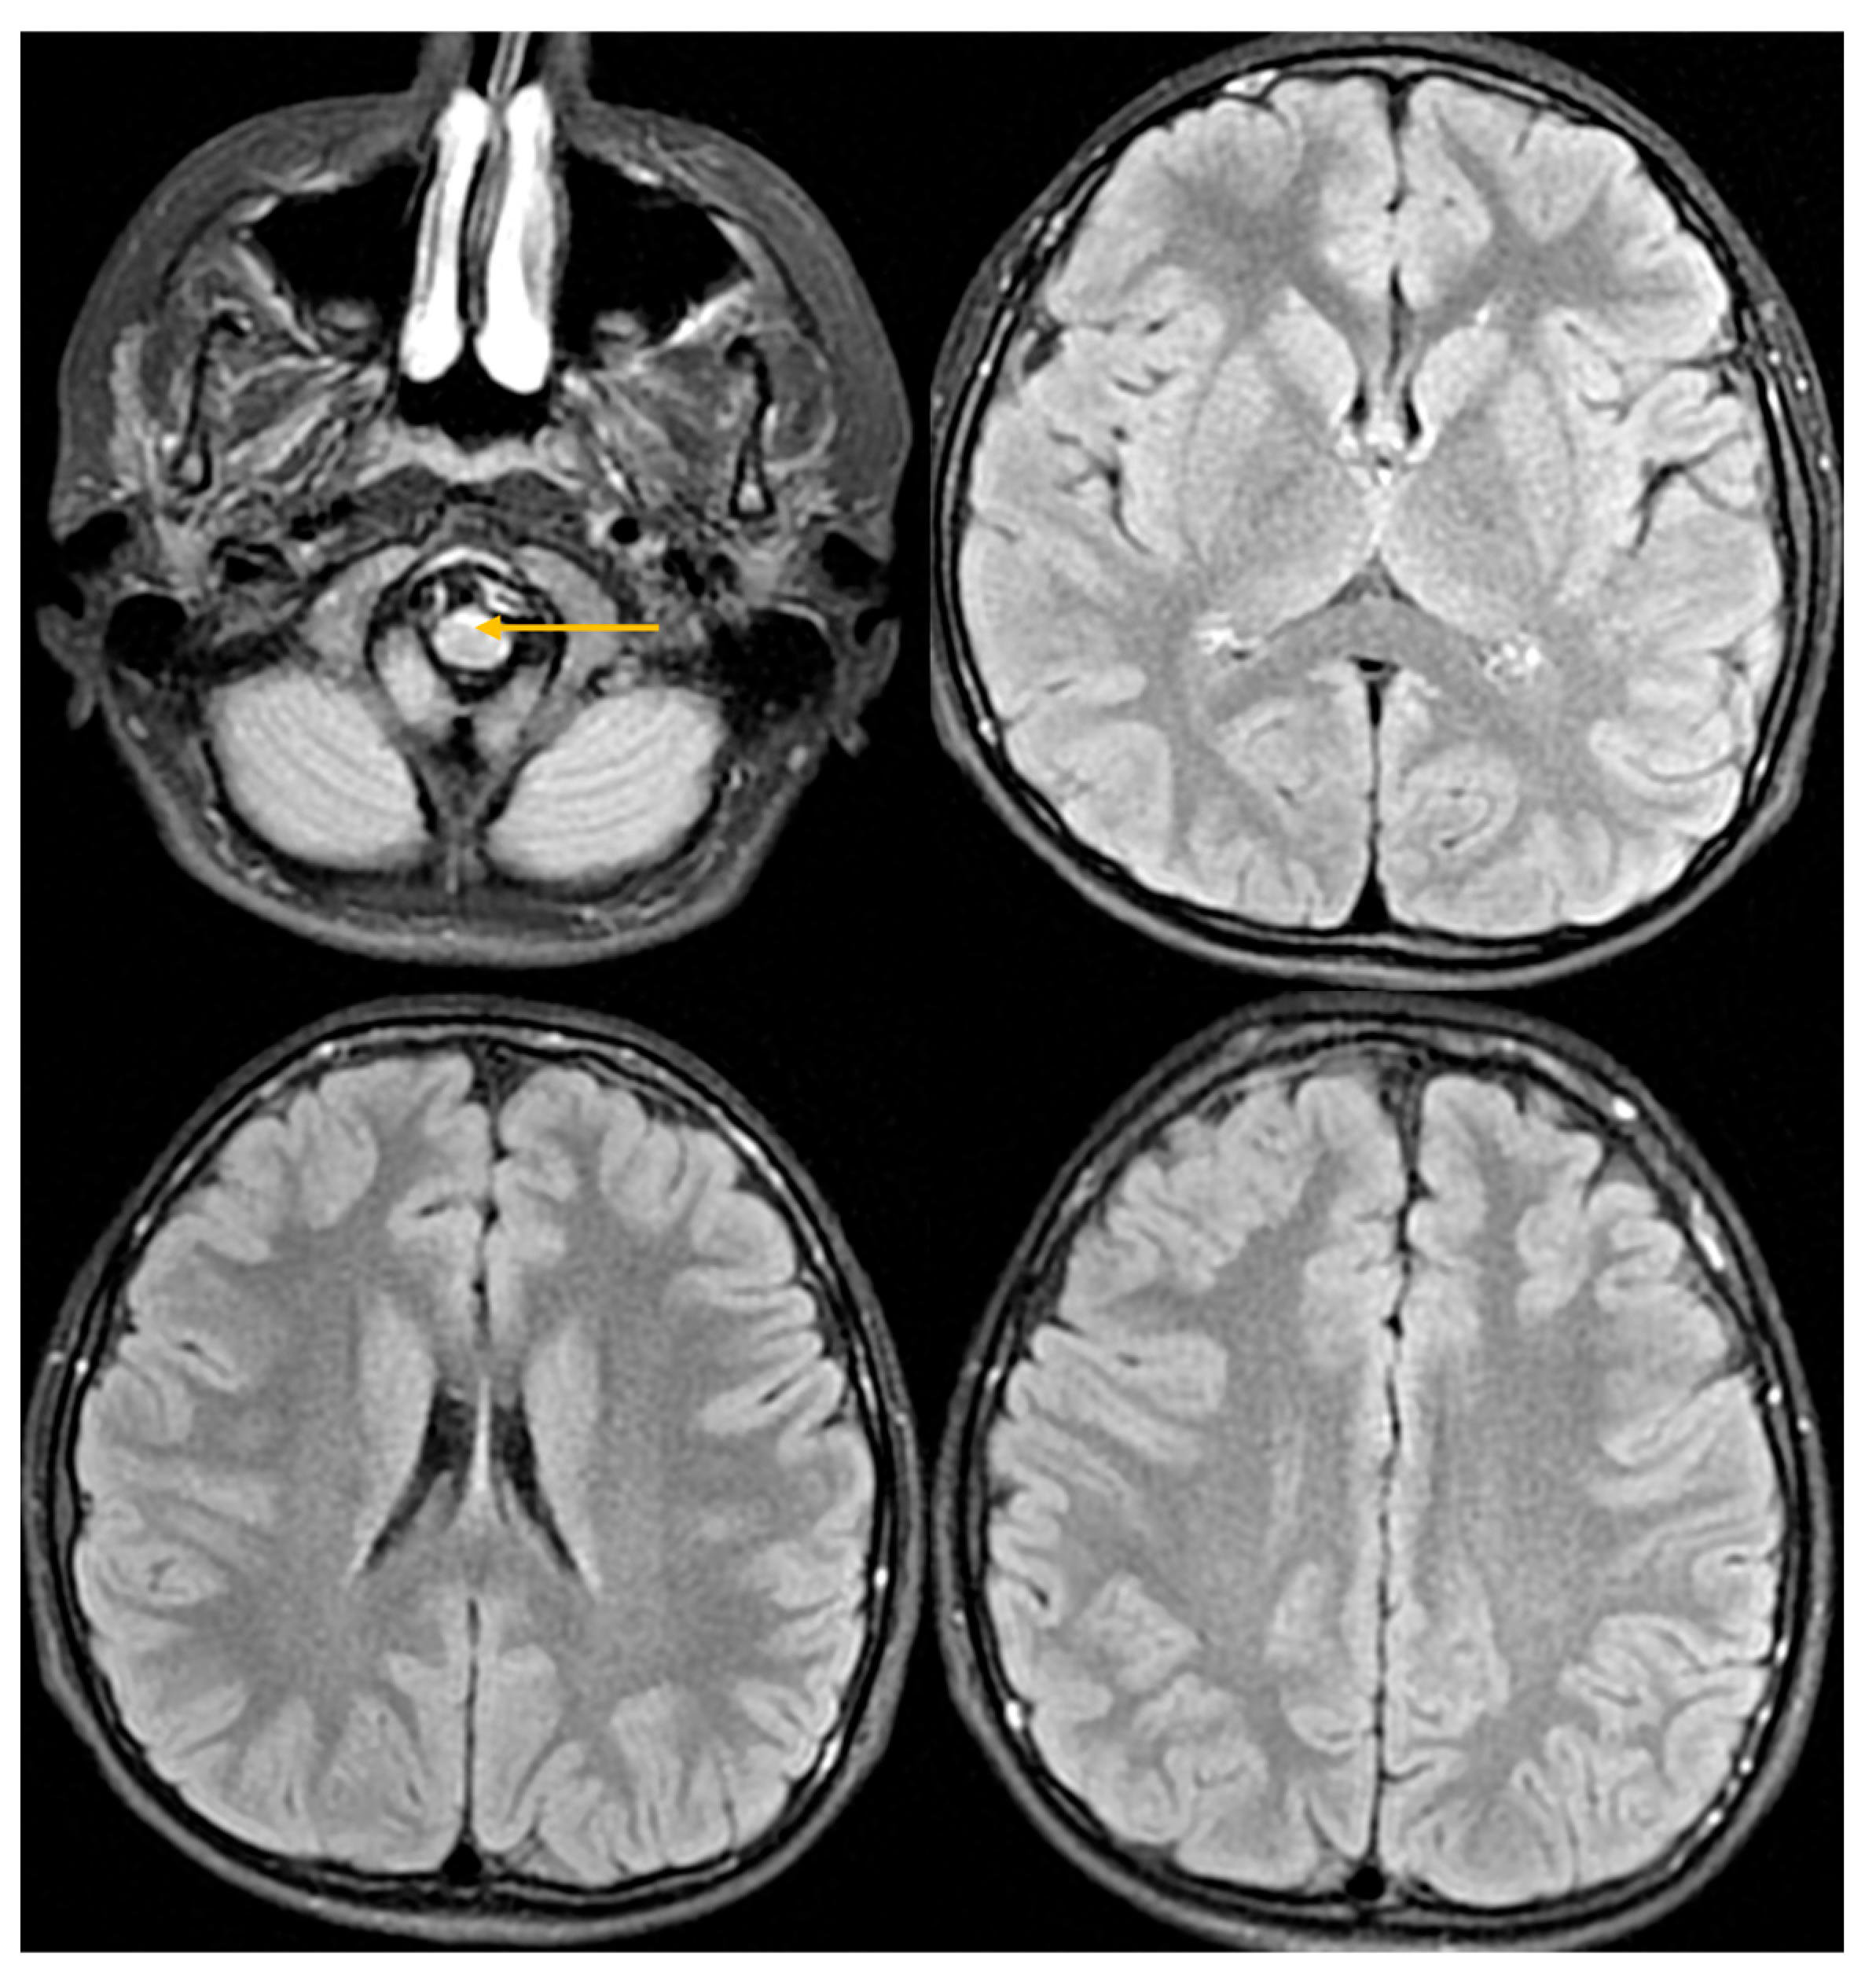

| Abnormal signal intensity of the anterior portion of the medulla oblongata | Yes | NA | Yes | Yes | Yes | Yes | Yes |

| Atrophy of the medulla | No | NA | No | Yes | Yes | Yes | Yes |

| Atrophy of the cervical spinal cord | Yes | NA | No | Yes | Yes | Yes | Yes |

| Signal abnormalities in the cerebellar white matter or hilus of the dentate nucleus | No | NA | No | No | No | No | No |

| Cyst formation in white matter around the anterior horn of the lateral ventricles | No | NA | No | No | No | No | No |

| Ventricular garlands | No | NA | NA | NA | NA | NA | NA |